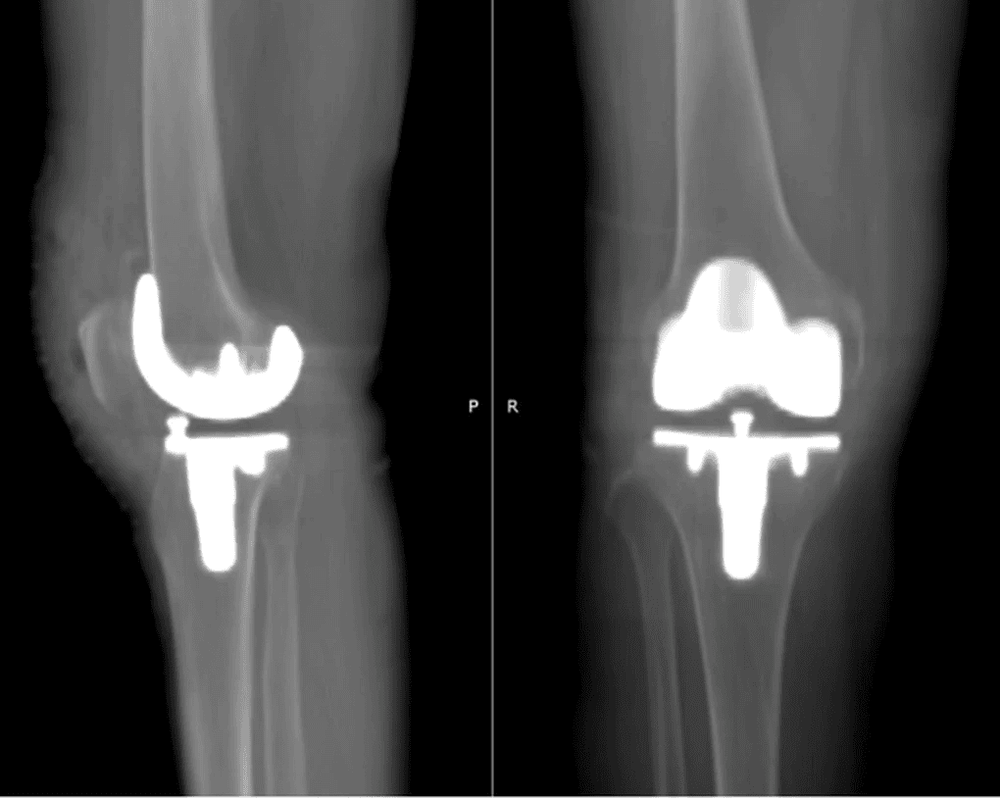

Chỉ sau 6 giờ sau mổ, người bệnh đã có thể đứng dậy, tập đi với khung hỗ trợ và tự di chuyển nhẹ nhàng. Kết quả chụp X-quang cho thấy khớp nhân tạo cân đối, đúng trục và vận hành ổn định.

Phim chụp X-quang của bệnh nhân sau ca mổ thay khớp nhân tạo